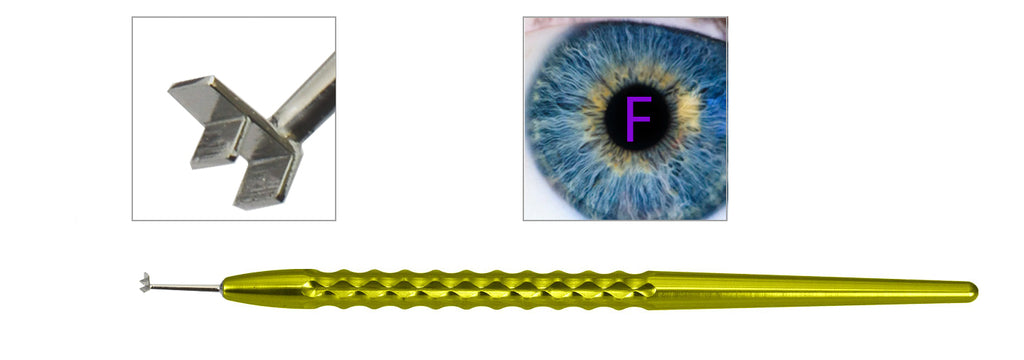

TMM211 DSEK/DSAEK Double-Ended Corneal Marker

Sale price$245.00

Regular price$295.00

In stock

In stock